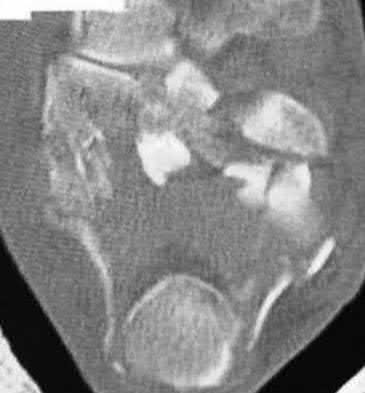

A 25-year-old female is involved in a motor vehicle collision. She presents with the isolated injury seen in Figures A through D. Her leg is swollen but her skin is intact. She has no clinical signs of compartment syndrome. Which of the following treatment options will allow for maintenance of fracture alignment and minimize the risk of soft tissue complications?

The patient presents with a closed distal third metaphyseal-diaphyseal distal tibia fracture with simple intra-articular extension. Immediate intramedullary nailing along with percutaneous fixation of the articular component provides appropriate restoration of length, rotation and alignment and minimizes the risk of wound complication.

Displaced distal third tibia fractures may be associated with simple intraarticular extension. Operative treatment of intra-articular distal tibia fractures has historically been performed with open reduction and internal fixation. Early open reduction and plate fixation of pilon fractures has been associated with high rates of infection and wound complication. In select patterns with simple articular extension, percutaneous screw fixation and medullary nailing may provide appropriate reduction with minimal soft-tissue risk.

Figures A and B demonstrate a distal third tibial shaft fracture with simple intra-articular extension. The axial and coronal CT cuts in Figures C and D further clarify the articular injury. Illustrations A and B demonstrate a comminuted distal third tibial fracture with simple intra-articular extension. Illustrations C and D are fluoroscopic images of the same injury after intramedullary nailing and percutaneous fixation of the articular component.